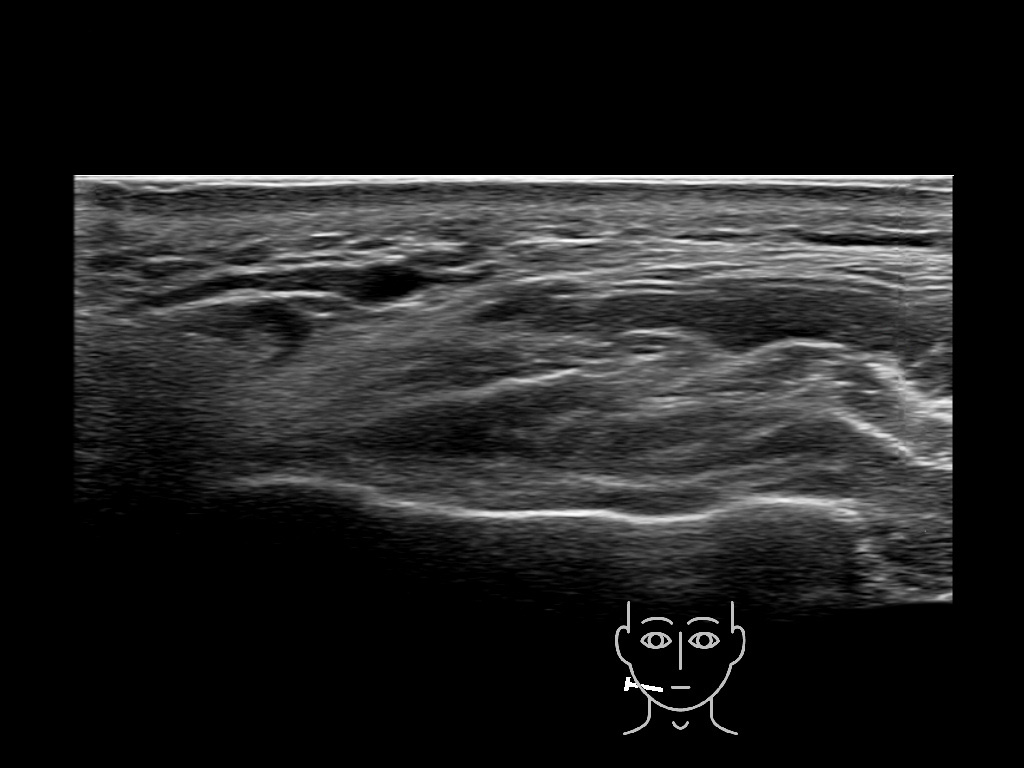

Filler deposits may end up unintentionally in the SMAS or fascial layers of the skin. Very often this will not lead to adverse events, however, adverse events ( nodules, migration / redistribution impaired muscle movement and smiling and malar edema) are are often related to filler ending up in the SMAS or fascia.

Study the first image to recognize the different layers. If you are sure about the layers, swipe to the second image to view the answer (if applicable).